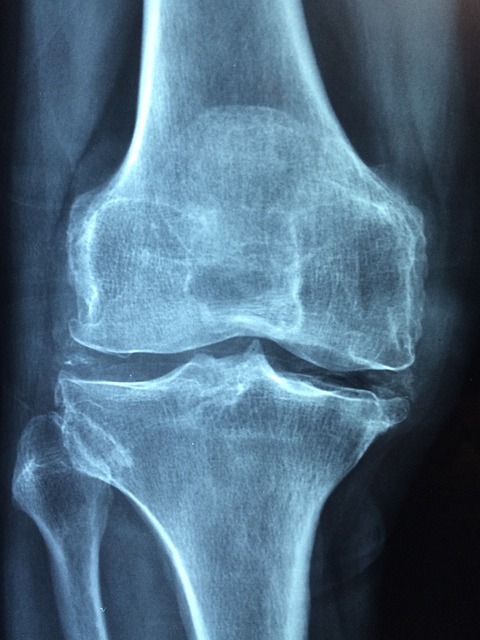

고관절 통증의 진단은 의학적 검진과 영상 검사를 통해 이루어집니다. 의사는 환자의 병력과 증상을 청취한 후, 관절의 움직임 범위와 통증 정도를 평가합니다. 필요에 따라 엑스레이, MRI, CT 스캔 등의 검사를 통해 뼈와 연조직의 상태를 확인할 수 있습니다. 이러한 진단 과정을 통해 정확한 원인을 파악하고, 적절한 치료 계획을 세울 수 있습니다.